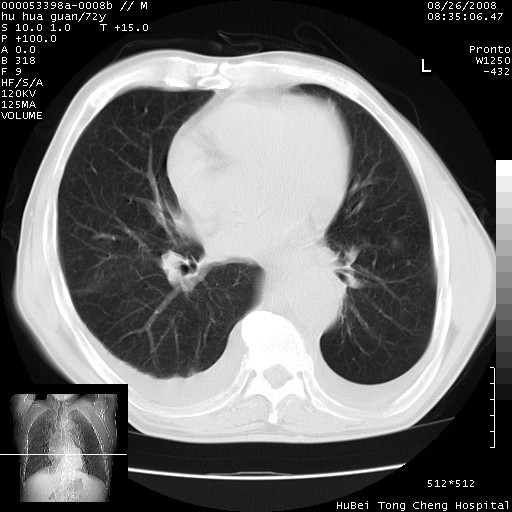

1、右上肺结节病变,肺泡癌不除外,请随诊;左下肺近后纵隔病变,考虑纵隔型肺癌侵犯大血管可能;

2、右下肺背段少许炎症,双侧胸腔积液,右下肺纤维索条。

可以明确的说。肯定不是主动脉夹层破裂出血!考虑为淋巴瘤或间叶组织来源的恶性肿瘤可能性大。右肺小结节建议薄层观察,如能发现恶性征象,那椎前改变就考虑为转移所致。至于双侧少量胸水乃静脉血回流受阻所致。